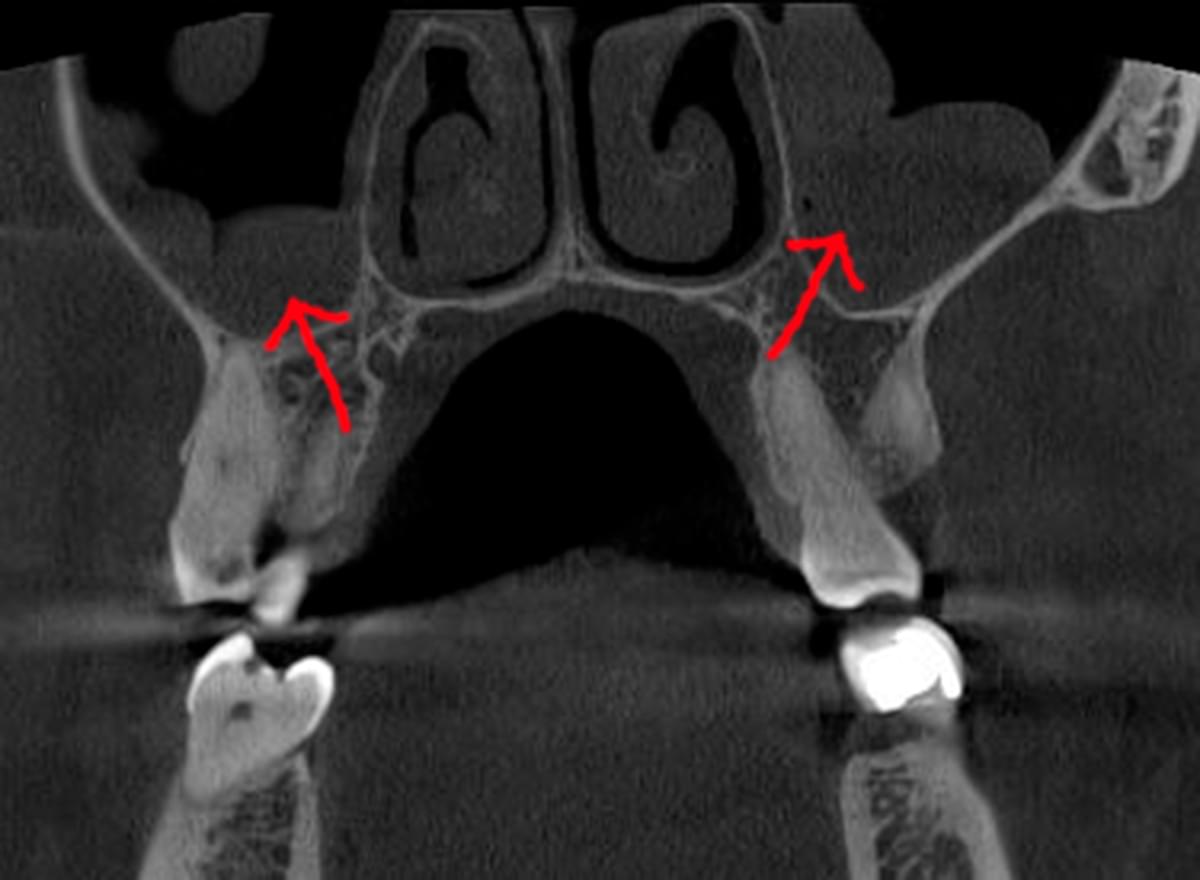

При плануванні імплантації лікарю важливо знати дві речі: об'єм кістки та точне розташування нервів.

КТ дозволяє провести віртуальну операцію: встановити імплант у програмі, виключивши будь-які ризики травмування пацієнта.

Часто причиною зубного болю є гайморит, і навпаки — причиною запалення пазух є хворий зуб. На звичайному знімку пазуха виглядає як темна пляма. На КТ ми бачимо стан слизової, наявність кіст або сторонніх тіл (наприклад, залишків пломбувального матеріалу), що критично важливо для правильного діагнозу.